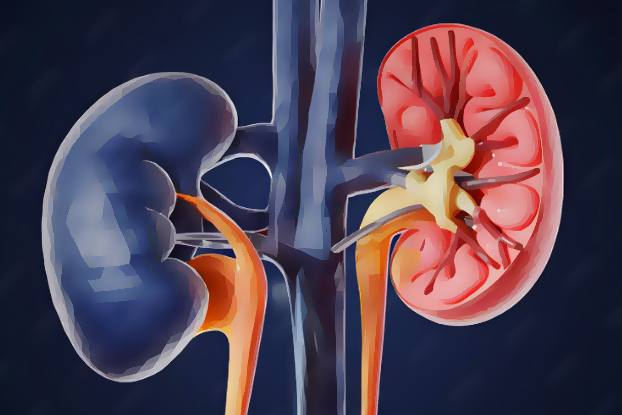

When it comes to advanced treatment for kidney, prostate, and urinary disorders, choosing a top-rated Urology hospital in Patna for laser & minimally invasive surgery is essential. Modern Urology has evolved significantly, offering painless, precise, and quick recovery solutions through advanced technology. Patients today prefer Hospitals that combine experienced urologists in Patna with cutting-edge laser equipment and minimally invasive techniques.

Comprehensive Kidney Stone Treatment in Patna

Kidney stones are one of the most common urological problems. A leading kidney stone hospital in Patna provides complete care including:

- Non-surgical kidney stone treatment in Patna

- Laser lithotripsy for stone removal

- Advanced Imaging for accurate diagnosis

Patients searching for the best hospital for kidney stone treatment in Patna benefit from high success rates and expert care.